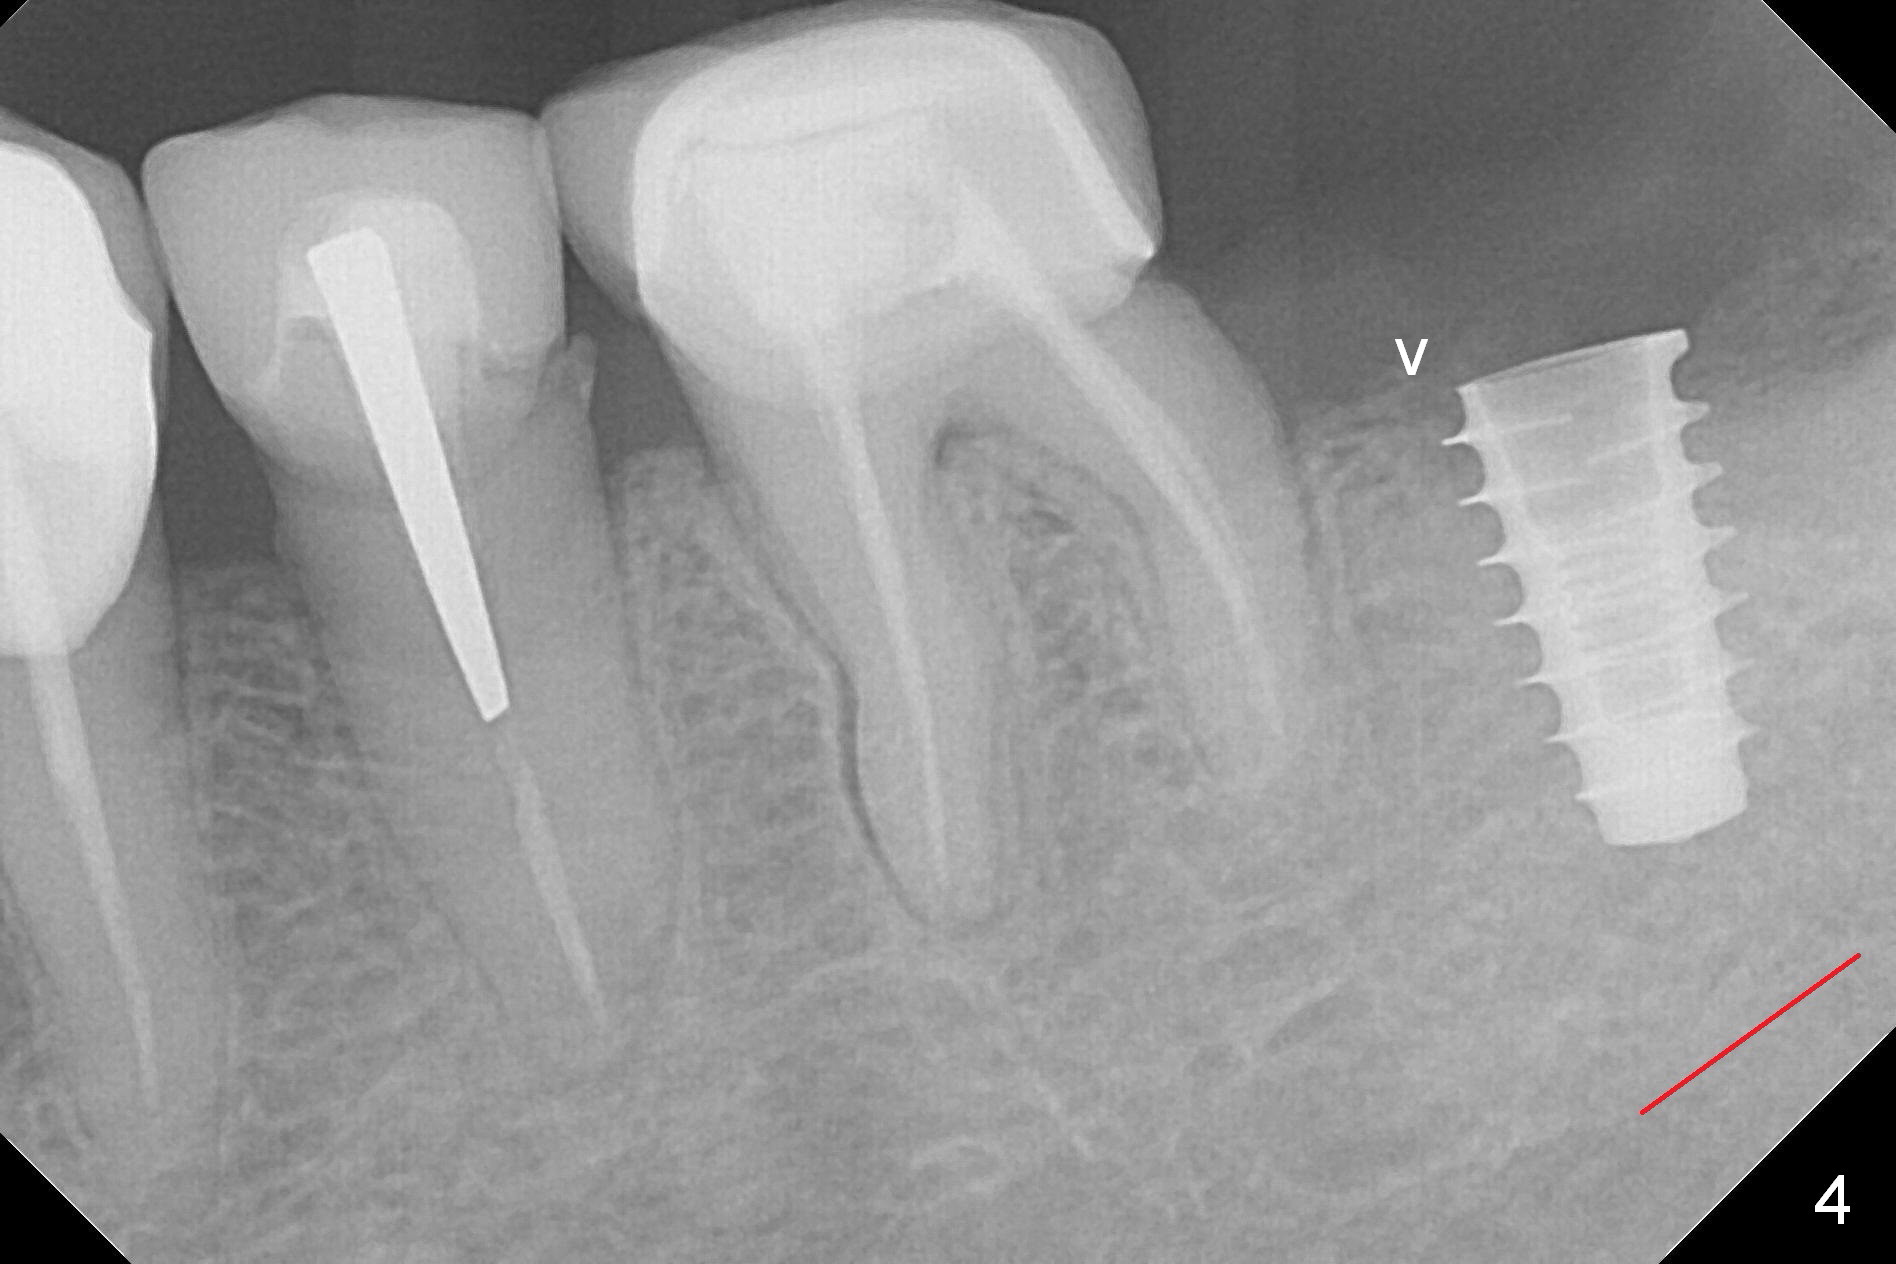

After 1.6 mm pilot drill (Fig.2) and 4.3 mm Magic Drill for 11 mm (gingival margin), a 4.5x11 mm dummy implant is placed with stability (Fig.3). Following Final Drill for 12/13 mm and 4.3 mm MD mesially, a 5x9 mm IBS implant is placed with 40 Ncm (Fig.4). Panoramic X-ray shows the placement is slightly supracrestal (Fig.5). In fact the implant is also placed slightly lingually. When the trajectory is changed, the implant loses stability. When a 5.5x9 mm implant is placed, no stability is achieved (Fig.6). After increase in osteotomy depth for 1-2 mm with MD 4.3 mm, the 5.5x9 mm implant barely obtains stability (~ 10 Ncm, Fig.7). Healing screw is placed. Osteogen plug is inserted in the distal portion of the socket; autogenous bone around the implant and Collagen plug to close the socket opening. Last suture and periodontal dressing are applied.

In fact, the mesial crest of the socket could be used as a more secure landmark (bony vs. soft tissue) for osteotomy depth (Fig.4 arrowhead) with drill stopper. To place the implant subcrestal, the initial osteotomy should be 1-2 mm deeper. When she returns 2 years 9 months postop, the wound has healed. The implant needs to be uncovered. Make sure to have clearance for a healing abutment. Use sensor 1 for PAs before and after uncover. The implant appears to be tilted distal. An angled abutment may be required. Take PA for seating confirmation. Guided surgery is preferable. The implant plateau is covered by the bone 2 years 9 months postop (Fig.8 *). The healing screw is removed with difficulty, while a 6x3 mm healing abutment is placed with resistance, probably related to interference from the distal crest (Fig.9 *). It is much easier with removal of the crest bone using surgical bur, because of clearance (Fig.10 *). It is the best to have a particular drill to remove the excess bone. There is no interference to insert and torque a 5x4(2) mm pair abutment 2 weeks post uncover (Fig.11). Due to poor trajectory (guide necessity) and tight proximal contact, the crown is not completely seated (Fig.12). However, the abutment screw is unlikely to get loose in the future.